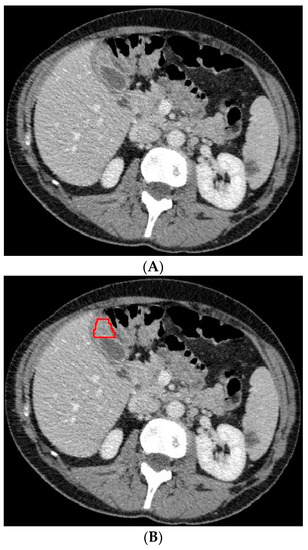

The 3D portal venous phase CT scans were pre-processed before being fed to the deep learning model. To improve contrast among abdominal organs, the CT scans were processed by a soft window centering at 50 HU with a width of 400 HU. To normalize the CT scans throughout the entire dataset, the images were resampled to the same spacing of 1.0, 1.0, and 2.0 by a linear interpolator. Using the software ITK-SNAP, the gallbladder on the CT scans was manually delineated by an abdominal radiologist who was blinded to the final diagnosis. Examples of the CT scans with segmented GBC and benign gallbladder disease can be found in Figure 2 and Figure 3.

Figure 3.

Axial CT slice (A) with an example of benign gallbladder disease (adenomyomatosis, encircled in (B)) and subsequent segmented gallbladder (C).